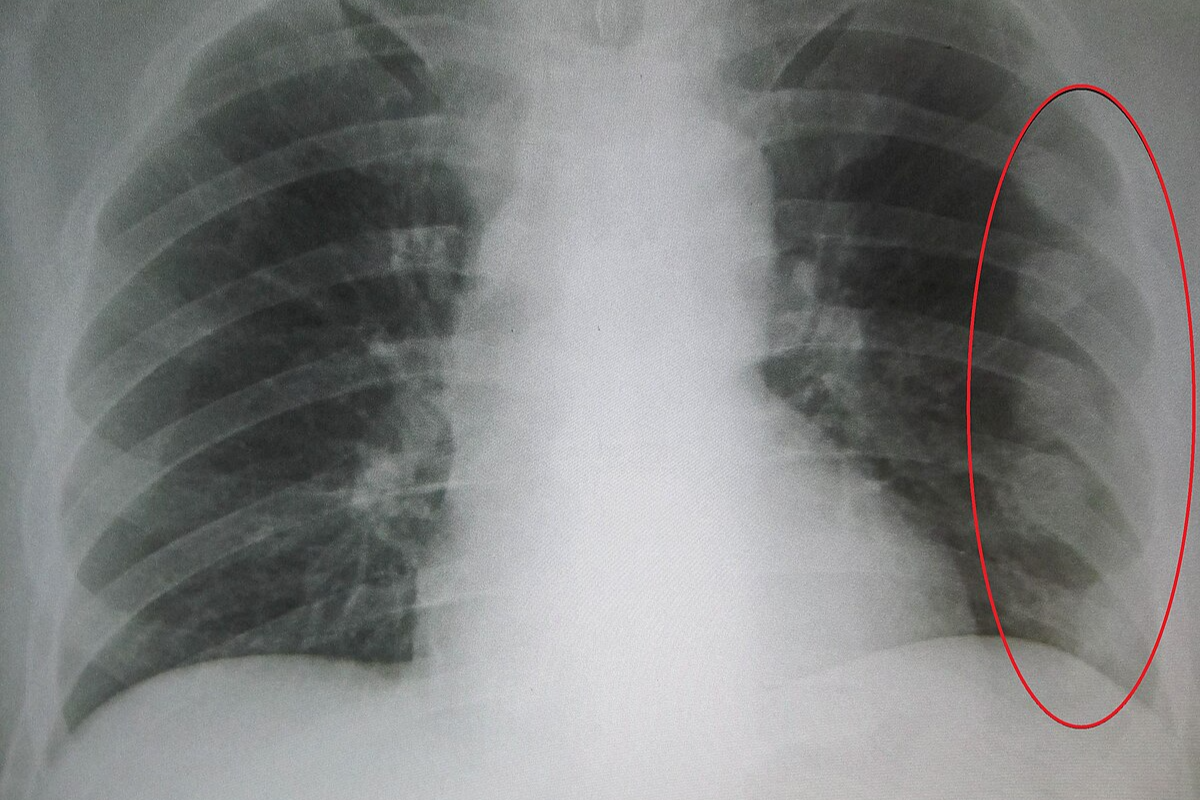

- X-ray: 기본적으로 뼈 손상을 확인하는 데 사용됩니다. 단순 골절은 X-ray로도 충분히 확인할 수 있습니다.